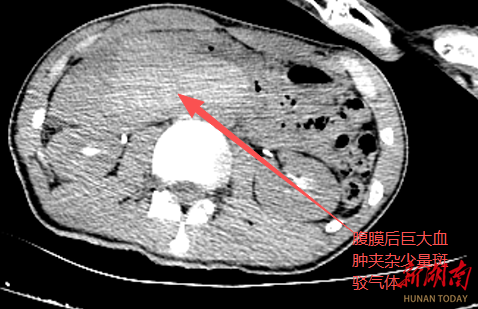

12-20 05:40...手术难度大且风险极高,决定紧急将其转往永州市中心医院。凌晨一点,患者抵达永州市中心医院时,已经表现出明显的失血和严重的腹膜炎症状。市中心医院急诊外科迅速响应,启动绿色通道,即刻集结专家团队进行紧急会诊。经检查后评估,诊断患者为十二指肠破裂、感染性休克及失血性休克并存、腹膜后巨大血肿。为避免患者因失血加剧及腹膜炎导致的多... 0